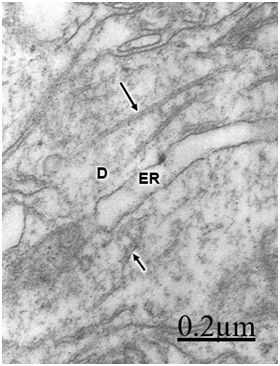

Figure 3 Brain trauma. Severe contusion of frontal region. Left frontal cortex.

Swollen shaft dendritic segment (D) displaying dilated smooth endoplasmic reticulum cisterns (ER), and intact (long arrow) and fragmented

Dendritic angulations, and nodular or segmentary dendritic swelling were earlier reported by Vaquero et al.55, Gallyas & Zoltay13 and Swann et al.31 in human epileptic dendrites. According to Vaquero et al.,55 the nodular dendritic swellings are due to alteration in the microtubular arrangement. Vacuolated dendrites inducing hydropic deterioration and degeneration of dendrites have been reported by Goldstein et al.6 in rat central nervous system after ethanol consumption, by Posmantur et al.86 after traumatic brain injury in rats, and by Sobaniec-Lotowska36 in rat experimental encephalopathy induced by valproate. Saito et al.87 found calcium accumulation in swollen dendrites following cerebral ischemia and traumatic brain injury. Gallyas & Zoltay13 considered that in cases of head injury, the beaded appearance of dendritic and axonal processes indicates an advanced stage of morphopathological damage. In addition, some neurons exposed to hypothermia, NMDA or ionophore also developed beaded dendrites (Emery and Lucas, 1995). Focal dendritic swelling was observed by Ferrer et al. (1998) in mucopolysaccharidoses types I, II and III. The focal swelling of dendrites is apparently similar to that observed in axonal processes also due to destruction of cytoskeletal network.88,89 Swollen and beaded dendrites have been widely reported in a large variety of pathological entities. Dendritic swelling was observed in stroke-prone spontaneously hypertensive rats,5 following intrathecal infusion of N-methyl-D-aspartate,90,91 in rats with neuroleptic-induced dyskinesias,92 and in rat brain during acute focal ischemia.32 Swann et al.56 postulated an ongoing excitotoxic injury of dendrites (dendrotoxicity) produced by excessive release of glutamate especially during seizures. In brain trauma there is also glutamate-induced citotoxicity,93 which supports Swann et al.94  hypothesis. According to Hasbani et al.94 the postsynaptic neuronal dendrite is selectively vulnerable to hypoxic-ischemic brain injury and glutamate receptor overactivation. Sodium, chloride, and water entry contribute acutely to excitoxicity dendritic injury, and calcium entry through NMDA receptors results in lasting structural changes in damaged dendrites. Lately Hasbani et al.94 expressed that in cerebral ischemia, neurons exposed to NMDA, kainite or oxygen-glucose deprivation suffer dendritic beading and lost of dendritic spines.